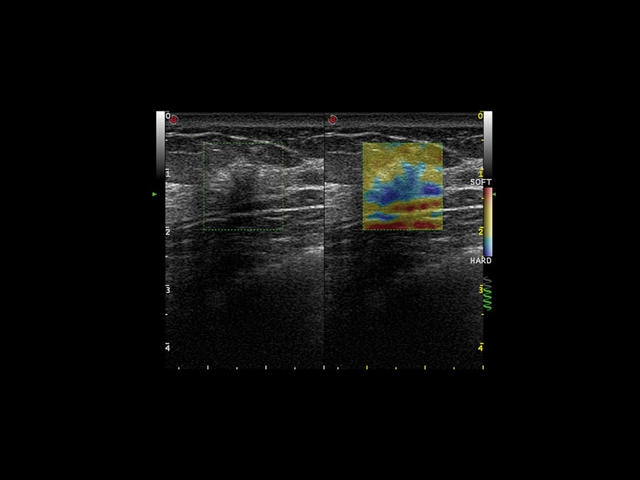

• Технология ElaXto для оценки эластичности тканей в реальном времени

Эластография:

Компрессионная

Компрессионная эластография:

Да

Эластография компрессионная ElaXto